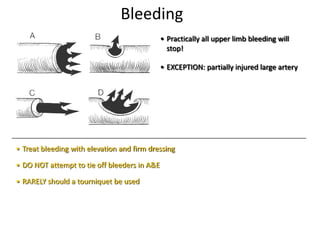

- Conditions that require emergency referral are discussed, such as bleeding, amputation, replantation, compartment syndrome, infections, and high pressure injection injuries. Proper management of these conditions focuses on rapid assessment and treatment to prevent further tissue damage.